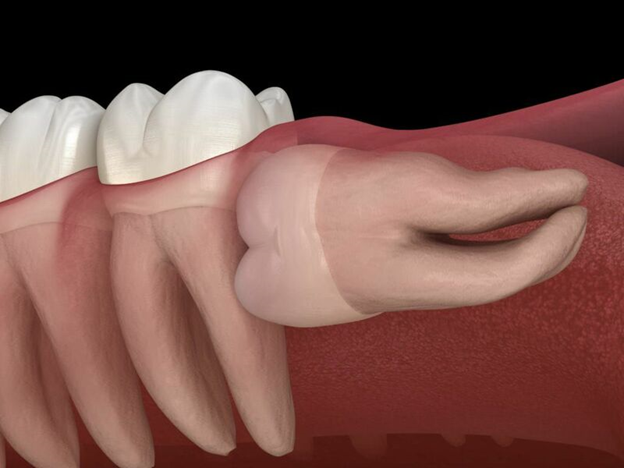

- Răng khôn mọc ngầm

- Toàn bộ răng nằm trong xương hàm, có thể đâm ngang hoặc chèn vào răng số 7 bên cạnh.

6. U nang thân răng

- Răng khôn mọc ngầm lâu ngày có thể hình thành u nang xương hàm.

- U nang gây phá hủy xương, làm tiêu xương vĩnh viễn, ảnh hưởng nghiêm trọng đến răng kế cận và cấu trúc hàm.

- Đây là biến chứng nguy hiểm cần được phát hiện sớm qua chụp X-quang/CT.